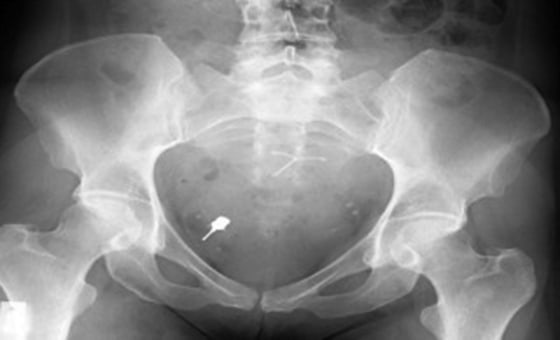

Such things would include the dental implant screwdriver that Gunaratnam removed a few years ago from the colon of a 47-year-old patient. It had been there for two months, ever since the woman’s dentist dropped it accidentally down her throat. She was told the object would eject on its own, but it never did, posing a serious threat to her health.

“The bowel is 1.5 milimeters thick and you have a spike sitting there,” Gunaratnam said. “If you move in the wrong way, if the bowel contracts in the wrong way, you have that spike perforating the bowel.”

He details four other case reports in which patient ingested endodontic files and crowns. It happens more often than you’d imagine, said Gunaratnam, who figures he sees 10 or much such cases every year.